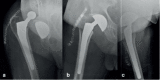

Methods: From March 2015 to March 2020, 138 patients were treated with Dualis Cup (Gruppo Bioimpianti-Peschiera Borromeo, MI, Italy) for a total of 141 implants (three cases were bilateral). The average age at the time of the surgery was 77. Patients' clinical and X-ray follow-up was at 1, 3, 6, 12 months and then once a year.

Results: Seven patients (4.9%) had complications which required a second surgery, but only one case (0.7%) of intraprosthetic dislocation (which required cup revision), was directly ascribable to the DM cup.

Conclusions: Improvements in design and materials of the third generation DM cups allowed both to reduce the rate of dislocations in high-risk patients (i.e., patients with neuro-muscular diseases and cognitive disorders, patients needing revisions, osteosynthesis failures, femoral neck fractures) and to achieve a survival rate similar to standard cups, ensuring a range of motion (ROM) very close to the physiological one. In our brief experience, Dualis Cups showed results comparable to those reported in the literature for Dual Mobility. If this data is confirmed by long-term studies, the use of DM cups could be extended even for young patients with high functional demands. (www.actabiomedica.it).